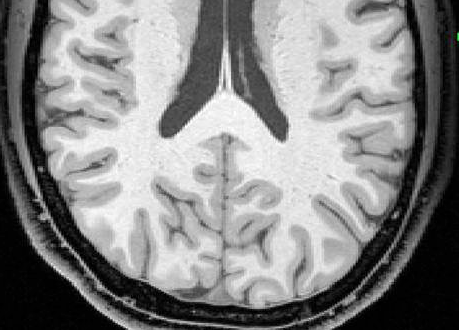

Blüml and colleagues have been studying preterm infants to learn more about how premature birth might cause changes in brain structure that may be associated with clinical problems observed later in life. Much of the focus has been on the brain's white matter, which transmits signals and enables communication between different parts of the brain. While some white matter damage is readily apparent on structural magnetic resonance imaging (MRI), Blüml's group has been using magnetic resonance spectroscopy (MRS) to look at differences on a microscopic level.

In this study, the researchers compared the concentrations of certain chemicals associated with mature white matter and gray matter in 51 full-term and 30 preterm infants. The study group had normal structural MRI findings, but MRS results showed significant differences in the biochemical maturation of white matter between the term and preterm infants, suggesting a disruption in the timing and synchronization of white and gray matter maturation. Gray matter is the part of the brain that processes and sends out signals.